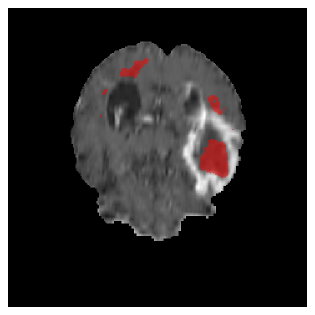

Appendix A Qualitative results

Figure 5 illustrates the segmentation evolution for the same BRATS patient in S2 sequence. The key difference here is that the best buffer-free strategy is EWC (=1), and training on BRATS data starts from episode 2 instead of episode 1 as BRATS is encountered at episode 2 in S2. The cumulative approach retains segmentation across episodes but continues to generate false positives, which become even more pronounced in the final episode. The naive approach, lacking a CL mechanisms, completely overrides previous knowledge, leading to failed segmentation in later episodes. EWC (=1) approach initially maintains segmentation but experiences a sharp decline in episode 4, where it fails to segment the tumor. In the final episode, it undersegments the lesion, missing a significant portion of the tumor. In contrast, the proposed approach consistently preserves segmentation across episodes. While initially introducing false positives, it gradually refines predictions, retaining the tumor region while minimizing misclassifications. It maintains clear tumor delineation by the final episode, demonstrating effective knowledge retention and adaptability throughout training.